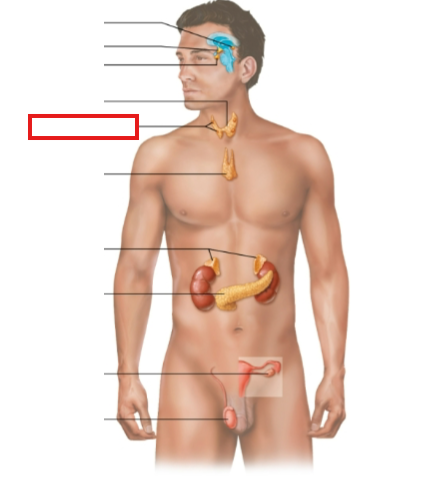

What structure is highlighted?

pineal gland

hypothalamus

pituitary gland

thyroid gland

parathyroid glands

thymus

adrenal glands

pancreas

ovary (female)

testes (male)